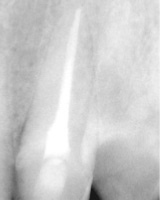

Toma de medida de la raíz.

Toma de medida radicular.